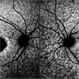

- Both the right and left Eye have fairly symmetrical, extrafoveal drusenoid-like flecks and focal and faint areas of RPE hyperplasia (in addition to mild NPDR and PPA) 57 yo WF referred for AMD vs Pattern Dystrophy that was diagnosed 10 years ago. Reported some slow progressive vision loss in both eyes for distance and near. Denies nyctalopia or hemeralopia. Background medical history includes HTN, CVD, and DM. No family history of eye problems. Denied pentosan use. Anterior segment showed moderate cataracts (OD>OS). Posterior segment exam showed macular changes and mild NPDR. The macular appearance showed a symmetrical, paramacular ring of fleck-like drusenoid material with some faint focal areas of RPE hyperplasia. Fundus Photos, AF, OCT were performed as well as a gene test. Further questioning showed revealed that her mother and maternal grandmother had both diabetes mellitus and sensorineural hearing loss. The patient developed diabetes in her teens, and some high frequency hearing loss in her early twenties. She had not had a previous genetic test or diagnosis of MIDD. Gene testing is pending for the mitochondrial component. Invitae's retinal panel, which does not include mitochondrial disorders, only showed a variant of uncertain significance, HMCN1. I discussed this case with Dr. Freund, and it is similar to a the case report : Inoue M, Kiss S, Freund KB. MACULAR PIGMENT RINGS AS THE PRESENTING FINDING OF MITOCHONDRIAL MYOPATHY, ENCEPHALOPATHY, LACTIC ACIDOSIS, AND STROKELIKE EPISODES. Retin Cases Brief Rep. 2015 Fall;9(4):260-4. doi: 10.1097/ICB.0000000000000182. PMID: 26200388.